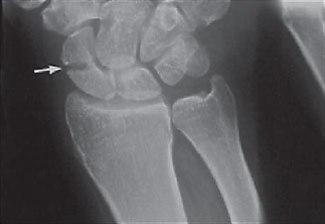

Etter skaden oppstår det umiddelbart smerter. Ofte ses ingen hevelse, men blødning i vevet kan føre til blålig misfarging på skadestedet etter noen dager. Legen får mistanke om tilstanden basert på skademekanismen, smertebildet og funn ved undersøkelsen. Typisk vil det fremkalle smerter hvis man klemmer i "snusdåsen" ved roten av tommelen - skafoidbeinet ligger like under huden her. Røntgen kan noen ganger bekrefte at det foreligger brudd (se røntgenbilde).

Imidlertid er bruddet ofte usynlig på røntgenbilder ved første undersøkelse. Hvis mistanken om brudd er sterk, men røntgenbildene er normale, henvises det vanligvis til CT eller MR for rask avklaring.